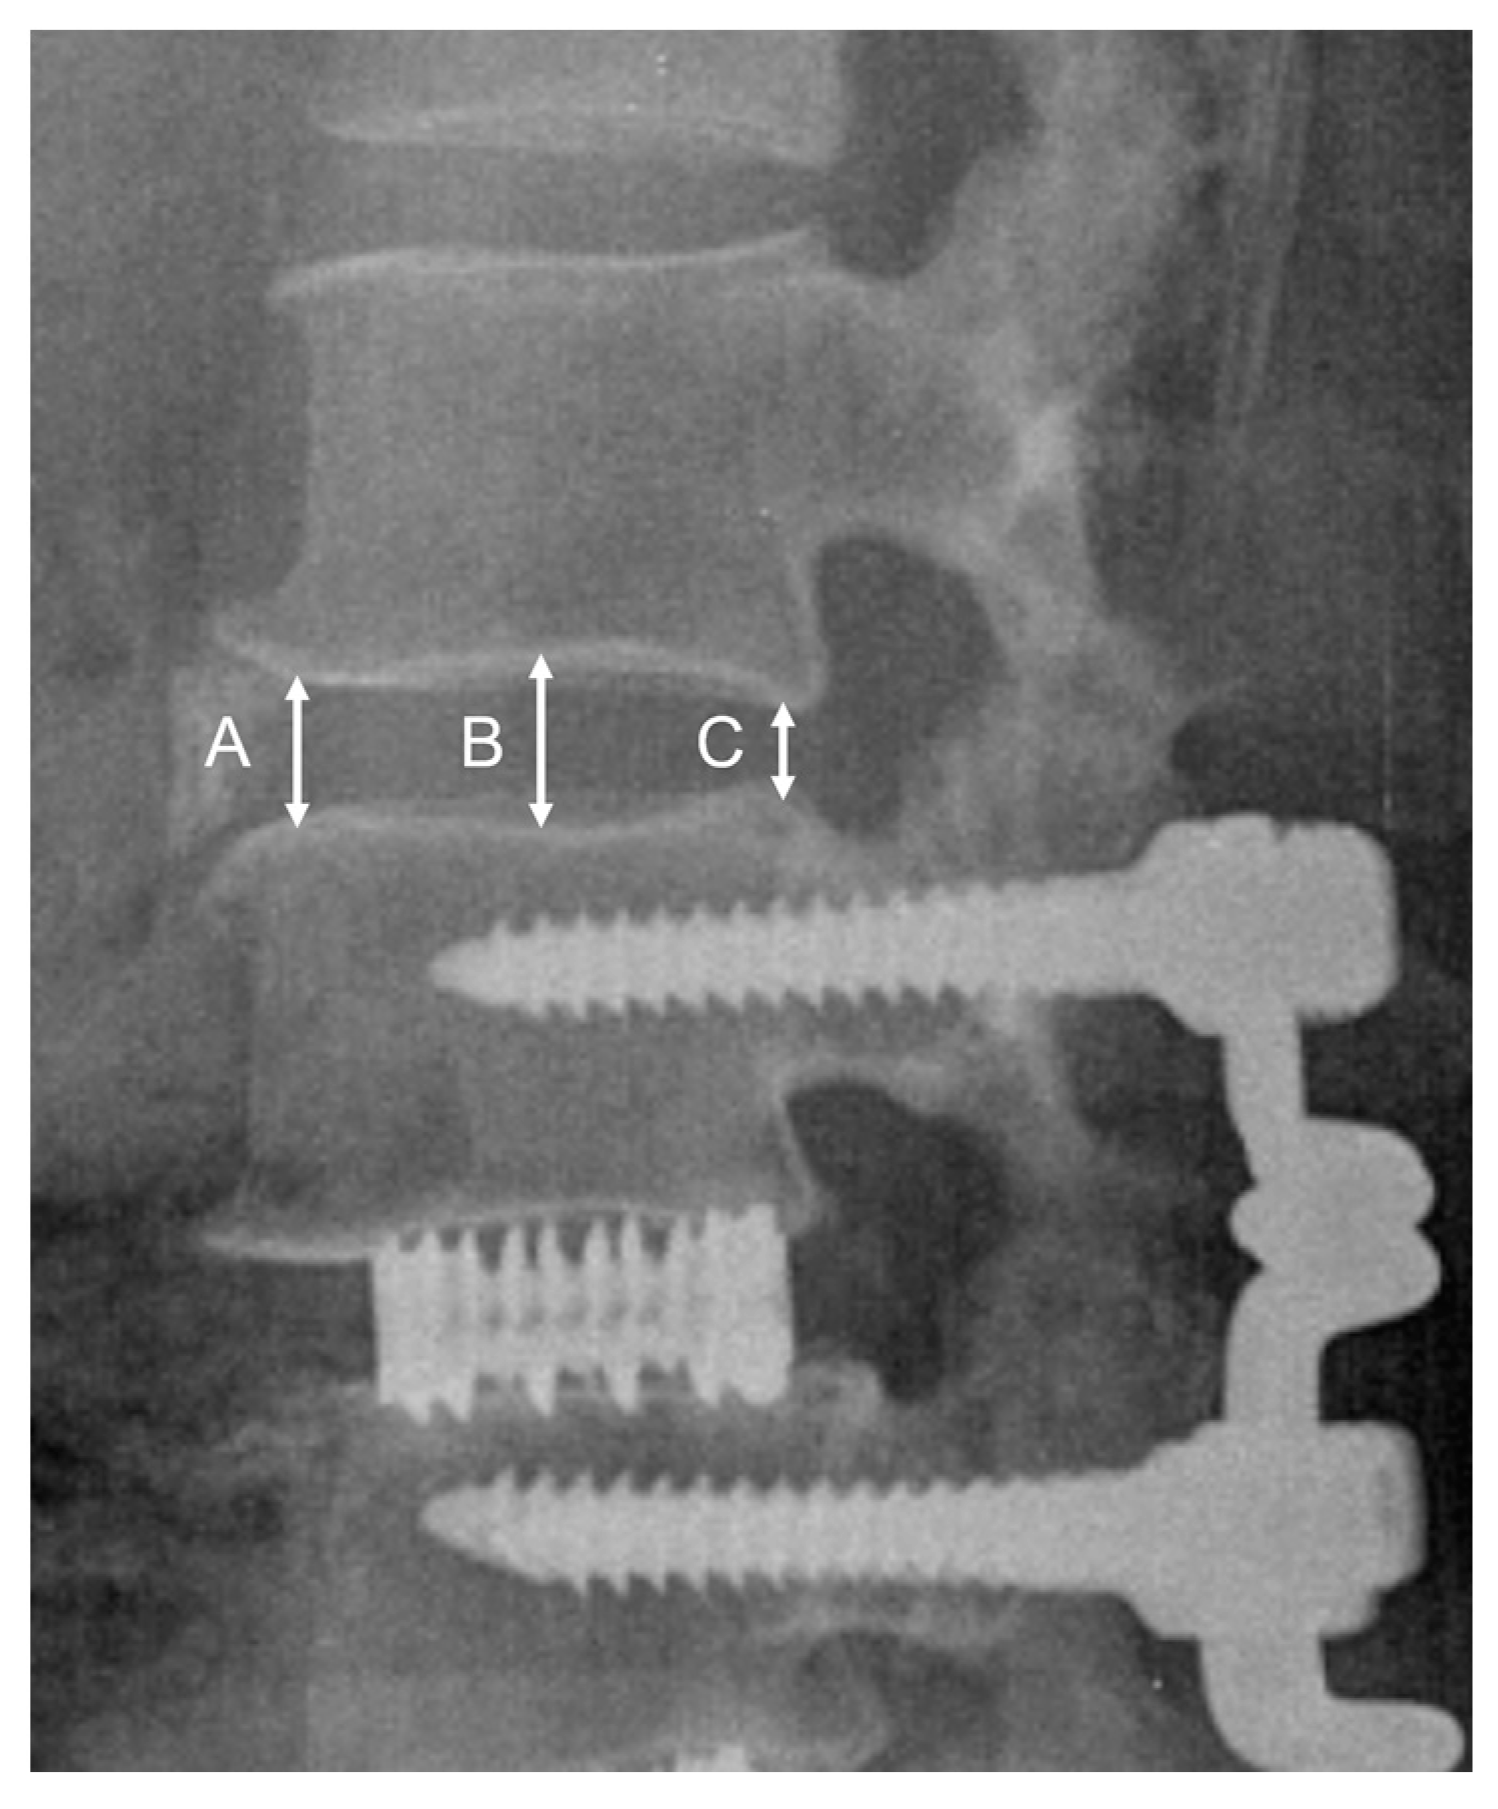

2.3. Radiologic Outcome Measures

| Upper disc height preservation (%) | 84.6 ± 15.2 | 87.3 ± 9.1 | 82.8 ± 20.0 | 63.4 ± 25.7 | 0.12 |

| Lower disc height preservation (%) | 89.2 ± 8.4 | 89.4 ± 8.6 | 89.1 ± 8.6 | 92.0 | 0.95 |